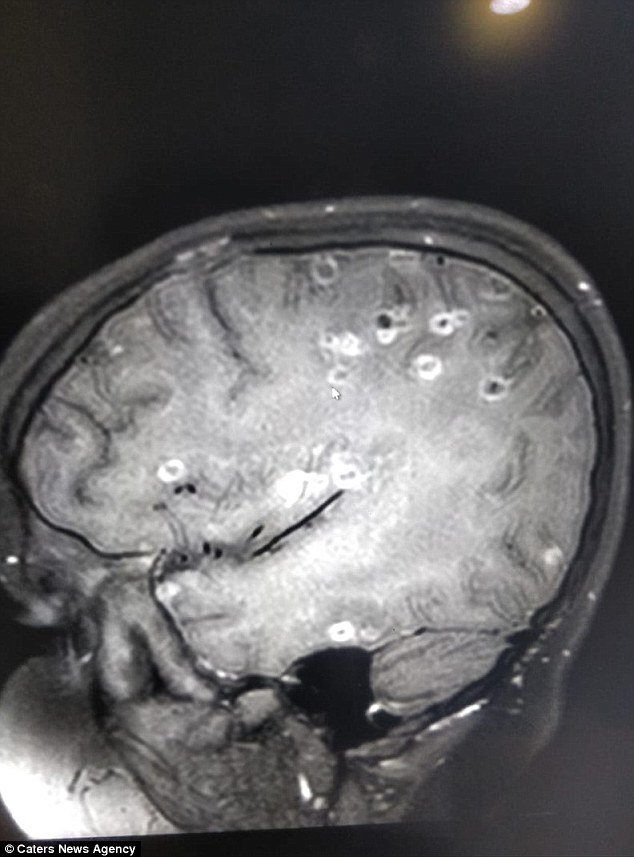

Ở đó, sau những lần chụp cắt lớp não bộ, cô bé được chẩn đoán là mắc chứng loạn thần kinh. Nguyên nhân chính là cô bé bị nhiễm sán dây nặng, trứng của chúng đi vào mạch máu từ dạ dày lên đến não và làm tổ ở đó. Lý giải cho nguyên nhân nhiễm sán dây, các bác sĩ cho biết, cô bé đã ăn trái cây chưa được rửa sạch và thịt chưa được nấu kỹ.

Praveen Gupta, giám đốc thần kinh tại Bệnh viện Fortis, cho biết: “Việc chụp cắt lớp phần não của cô bé đã cho thấy hơn 100 chấm trắng hình thành do trứng của sán dây. Việc cơ thể bị xuất hiện các triệu chứng sưng tấy và nhiễm trùng chính là do ăn phải thực phẩm có chứa trứng sán.

Khi trứng xâm nhập não bộ qua hệ thần kinh, chúng gây ra chứng loạn thần kinh, biểu hiện thông qua những cơn đau đầu dữ dội, những cơn co giật và tâm lý bất ổn. Có thể nhiều người không biết, nhưng hiện tượng trứng sán dây phá hoại chức năng não bộ là rất phổ biến”.